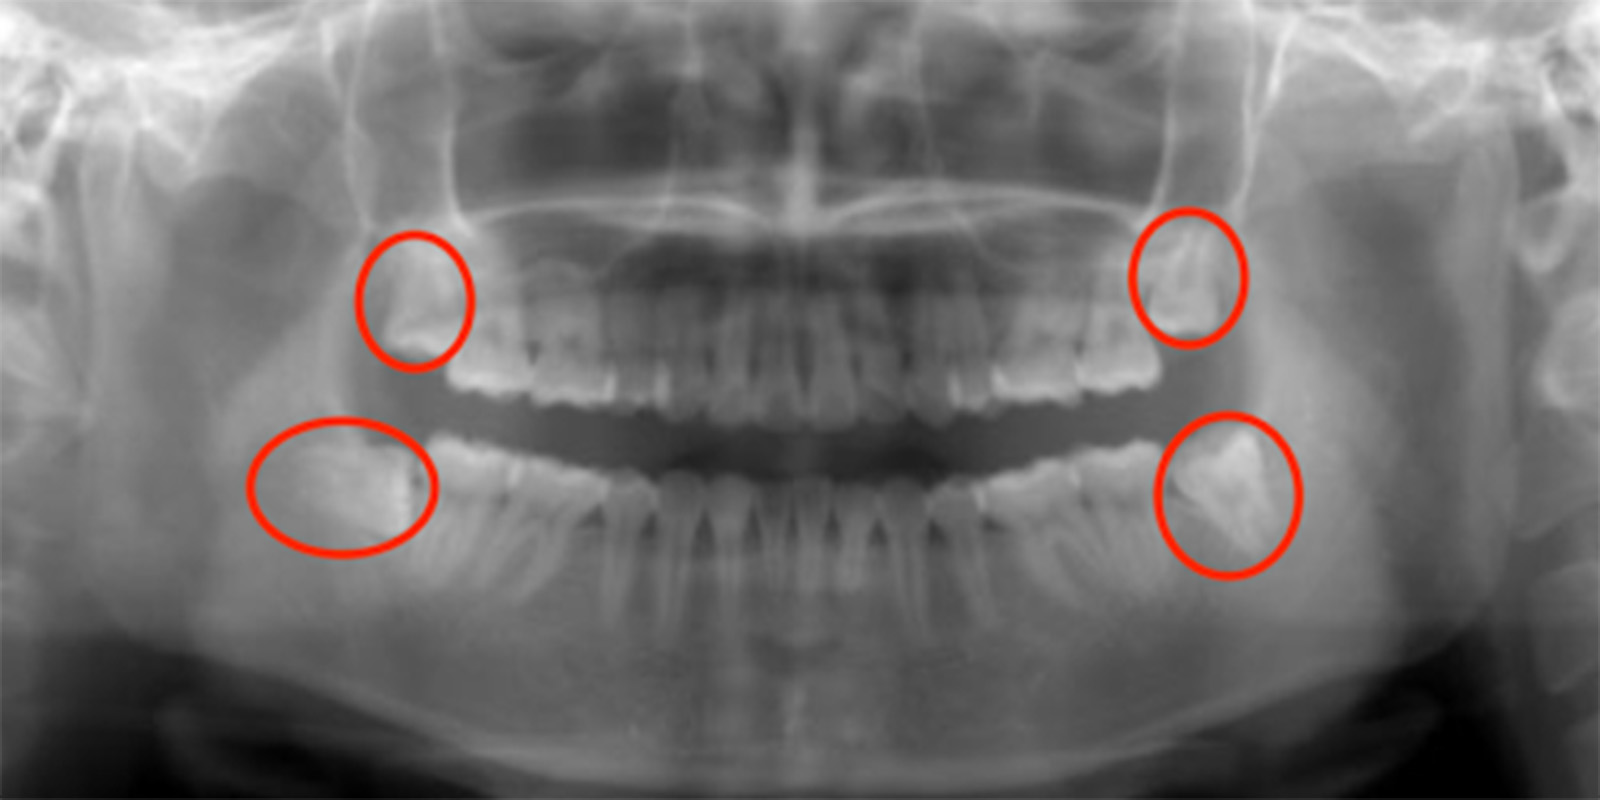

親知らずがあるレントゲン画像

基本的には、どのようなケースでも

対応します

ただ根の先に下顎管が触れているようなケースであれば2回で対応したりしますが歯の頭の部分が下顎管と触れているような稀なケース、親知らず周りが嚢胞になってしまっているケース、全身疾患がある方、外科処置が困難な方に関しては大学病院を紹介させていただくこともあります。